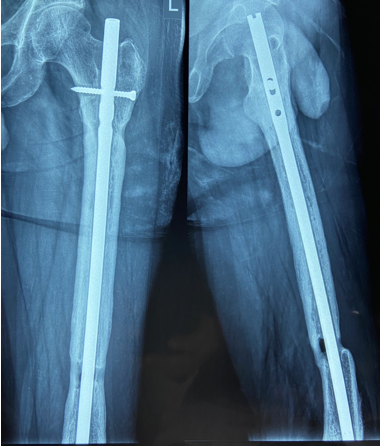

In a series of delayed union with internal fixation over 47 patients regardless of the fracture sites communition or inadequate fixation, had union in all patients including a case of infected nailing of femur. These patients had reported to Dr. S S Jha three to seven months after internal fixation at other centers. None of these patients were willing to submit themselves for further surgical intervention. Teriparatide 20mcg daily through subcutaneous route was started in all patients with adequate supplementation of vitamin D and calcium. Evident radiological bony union was perceptible after three months with clinical improvement in the initial presenting symptoms of the patients and the osseous consolidation was invariably observed radiologically within four to six months. It was only in six patients that Teriparatide was continuously used for one and half years for reasons of general debility, elderly age and osteoporosis. Radiographs of three difficult cases are being displayed from the series.

Case 1([Figure 1], [Figure 2], [Figure 3], [Figure 4], [Figure 5], [Figure 6], [Figure 7], [Figure 8], [Figure 9])

- Case 1([Figure 1], [Figure 2], [Figure 3], [Figure 4], [Figure 5], [Figure 6], [Figure 7], [Figure 8], [Figure 9])